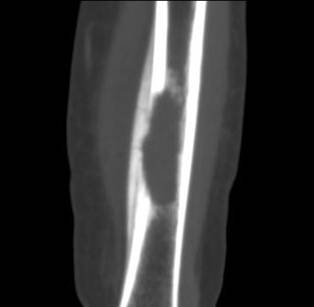

男孩,5岁,左小腿疼痛,肿胀,活动受限20天。

左胫骨中下段见一长卵圆形骨质破坏区,走形方向与胫骨长轴一致,边缘轻度硬化,内后侧骨皮质破坏,伴明显骨膜增生,破坏区内呈软组织密度。未见明显软组织肿块。

左胫骨中下段见一不规则虫蚀样骨破坏,走形方向与胫骨长轴一致,边缘轻度硬化,伴明显骨膜增生,ct见破坏区内见磨玻璃样密度,其旁软组织钟胀,内见不规则钙化。

左胫骨中下段见一不规则虫蚀样骨破坏,走形方向与胫骨长轴一致,边缘轻度硬化,伴明显规则的骨膜增生,ct见破坏区内见磨玻璃样密度,其旁软组织钟胀,内见不规则钙化。

病史资料不完善,根据年龄、部位、及影像学表现,主要表现胫骨骨干囊性骨质破坏,骨皮质受累,局部骨膜反应,未见骨膜破坏及瘤骨,未见放射状骨针。 首先要考虑胫骨转移瘤,建议进一步检查,除外视网膜母细胞瘤,神经母细胞瘤,肾母细胞瘤,肾上腺等恶性肿瘤骨转移。排除转移瘤后考虑嗜酸性肉芽肿可能性大,患者年龄5岁,尤文氏瘤不太考虑,骨肉瘤也不太符合,骨髓炎待排,影像表现不太支持。建议进一步检查,除外原发恶性肿瘤胫骨转移后,考虑嗜酸性肉芽肿。必要时穿刺活检。